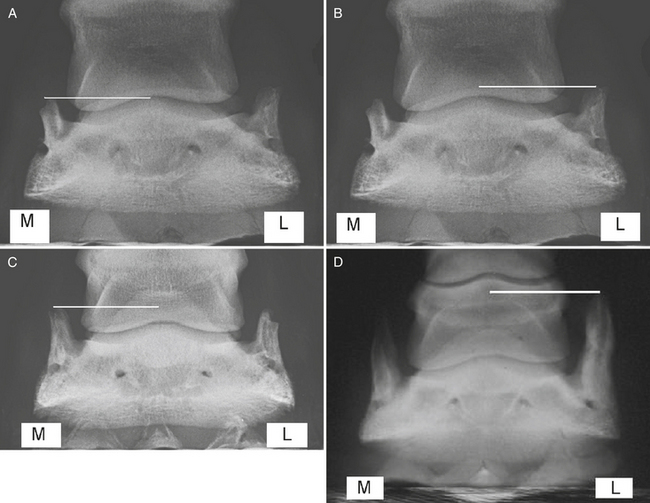

Fig. 3 Dorsopalmar radiographic view of a foot (medial is to the left in A–D) with grade 2 ossification of the medial cartilage of the foot (white line). B, Dorsopalmar radiographic view of a foot with grade 3 ossification of the lateral cartilage of the foot (white line). C, Dorsopalmar radiographic view of a foot with grade 4 ossification of the medial and lateral cartilages of the foot (white line). D, Dorsopalmar radiographic view of a foot with grade 5 ossification of the lateral cartilage of the foot (white line). M, Medial; L, lateral.(Reproduced from Veterinary Key)